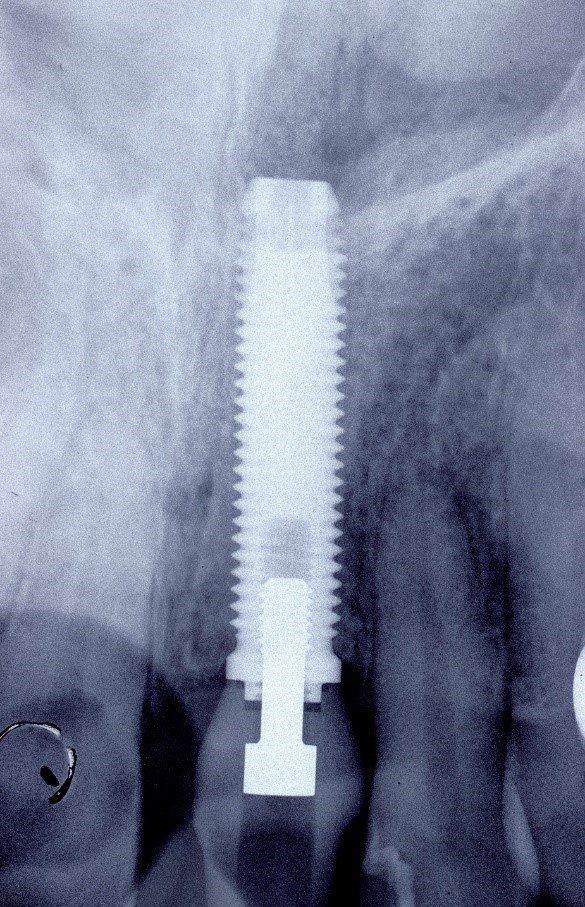

Nel 1994 una paziente di 28 anni subì la frattura dell’incisivo centrale superiore sinistro precedentemente trattato endodonticamente

Un caso analogo al precedente.

Una giovane signora di ventotto anni subisce nel 1996 la frattura dell’incisivo centrale superiore destro

in precedenza trattato endodonticamente

Radiograficamente è visibile il trattamento endodontico dell’incisivo laterale sinistro coinvolto anch’esso nel trauma. Sono visibili inoltre i dispositivi ortodontici necessari pe la sua estrusione al fine di recuperare l’ampiezza biologica, ovvero al fine di mantenere tre millimetri di tessuto dentale sano oltre il margine gengivale